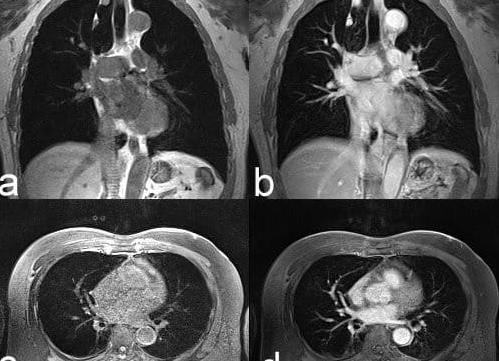

Легкие человека – для изучения и детального обследования очень сложны, ввиду того, что в легочных тканях содержится воздух, а это значительно затрудняет визуализацию сосудов. МРТ легких – показывает картинку двух проекций сбоку и спереди, что не позволяет «протий мимо» структурных клеточных изменений, патологических образований. Диагностика дает информацию в сагиттальной и фронтальной областях, что позволяет понять, с чем столкнулся пациент и врач, как это лечить и контролировать.

В материале узнаем также, делают ли МРТ бронхов и легких. Диагностическая процедура МРТ представляет собой информативный метод, отображающий структурные изменения, а также позволяющий выявить патологические новообразования в легких и бронхах. Магниторезонансная томография позволяет получить снимки в виде срезов диагностируемых органов, по которым можно выявить признаки отклонений и патологий.

Для исследования легких и бронхов применяются контрастирующие вещества. Обычно в качестве такого вещества применяют магневист, который обладает большей плотностью, по отношению к остальным, а также хорошо переносится организмом. Методическое диагностирование МРТ легких показывает следующие патологии и отклонения:

- выявляет наличие патологических инфильтратов;

- определяет формы и границы очагов воспалений;

- позволяет определить вид новообразования;

- определяет степень врастания опухолей в ткани соседних органов;

- выдает результаты исследования в трехмерном изображении.

МРТ легких и бронхов позволяет не только выявить возникновение опухолей, но еще и дать четкую картину разграничения и отличия опухолевых процессов от прочих видов воспалительных патологий. Именно посредством такой возможности данный вид обследования позволяет получить большие перспективы в будущем.

Злокачественная опухоль определяется по наличию более плотных участков ткани. Если же на снимке обнаружено несколько подобных участков, то можно говорить о том, что опухоль уже дала метастазы. МРТ может показать каверны при туберкулёзе лёгких и кистозные образования при поражении паразитами. По результатам исследования можно выявить воспаление плевры и жидкость, которая собралась в плевральной области.